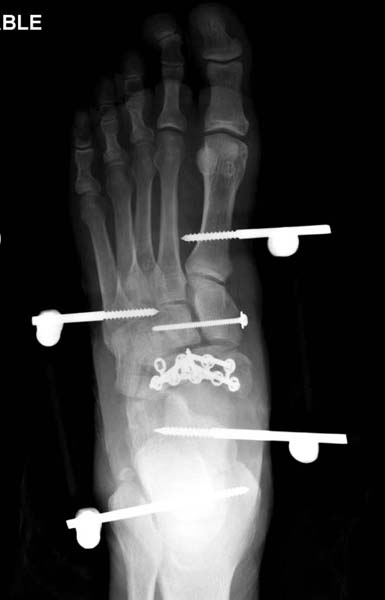

В нашем случае, травма в результате коллапса крыши. Открытый перелом. Ургентные Irrigation and Debridment, дистракция наружным фиксатором. В госпиталях первого уровня редко бывает изолированная травма, и на другой стороне повреждение стопы с переломом навикулярной кости. После обработки раны - вакуум и двухсторонние наружные фиксаторы.

Через три дня оперирована стопа и для нейтрализации сил колонн оставили наружный фиксатор.